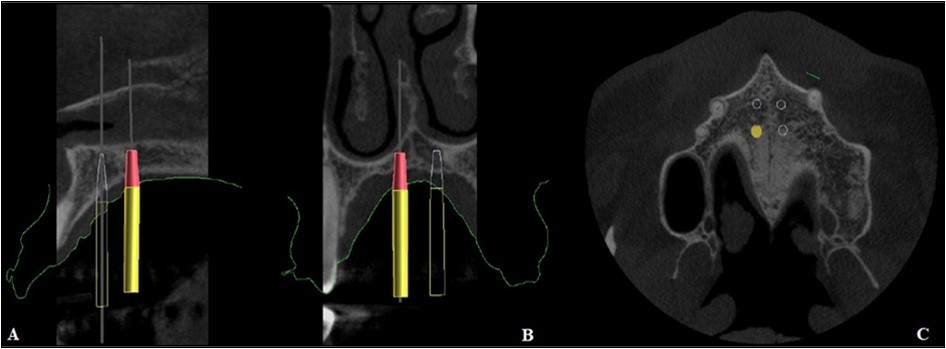

The precise position and angulation of the mini-implants is replicated by 4 cylindrical metallic guides taking into consideration the following parameters: bone thickness, soft tissue thickness and anatomical surrounding structures. The most appropriate site for the placement of mini-implants is: 3 mm lateral to the suture in the first premolar region. (Figure 3,Figure 4)

Figure 3.Positioning of the 4 mini-implants, visualized on the basis of the intraoral scan

Figure 4.Positioning of the mini-implants on CBCT, A. Sagittal section, B. Coronal section, C. Axial section